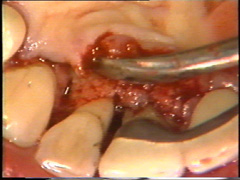

Observese como se ha eliminado el tejido de granulación en el segundo premolar.

Eliminación del tejido de granulación

Las superficies de la raíz se limpian (raspado y alisado radicular) cuidadosamente y el tejido de granulación en los defectos óseos (cráter) es eliminado. En la superficie bucal del segundo premolar hay  un cráter óseo y cálculo en la supericies dental adyacente.

El cálculo del segundo premolar  está unido firmemente a la superficie dental y es un proceso tedioso el quitarlo.